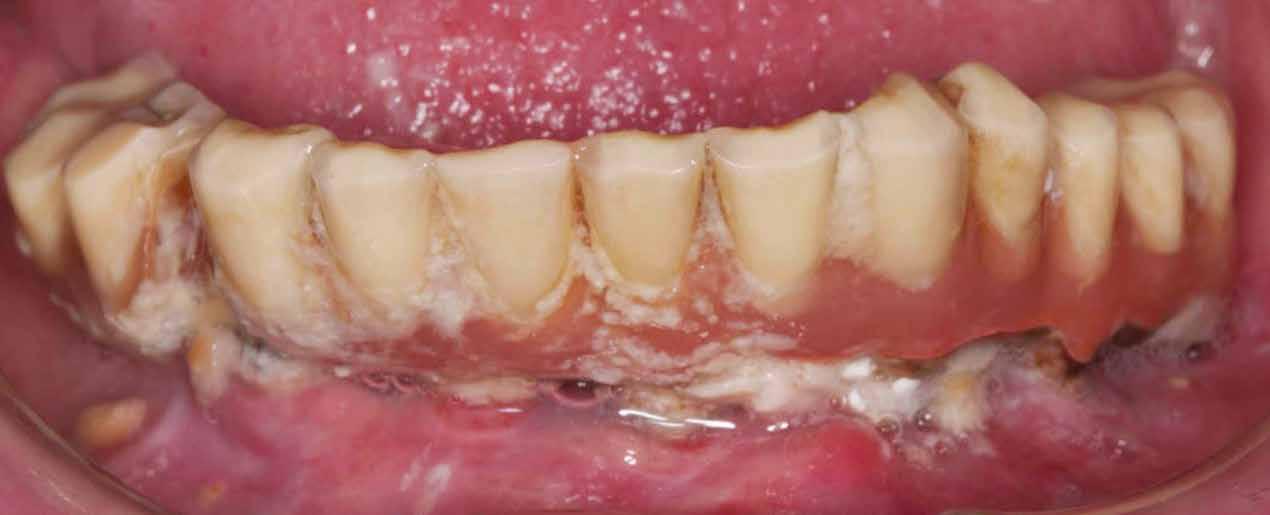

6. ábra: Klinikai helyzet a kezdeti vizsgálat során. 9 mm mély periimplantáris szondázási mélység, szondázási vérzéssel. Az arc periimplantáris nyálkahártyáján sinus felőli szivárgás figyelhető meg. A periimplantitis diagnózisának felállítása előtt körülbelül 4 évvel, amikor a pácienst kezelésre utalták, cementált fogpótlást helyeztek el ezen a Straumann lágyrész-szintű implantátumon.

7. ábra: Röntgenfelvétel a marginális csontszintekről az implantátumnál a kezelés előtt. Meziális és disztális csontvesztés figyelhető meg, amely az implantátum második menetéig terjed. Figyelje meg az implantátum disztális felszínén lévő radioopak anyagot (felesleges rögzítőcement)! Figyelje meg a 11-es fog meziális felszínén lévő fogkövet is!